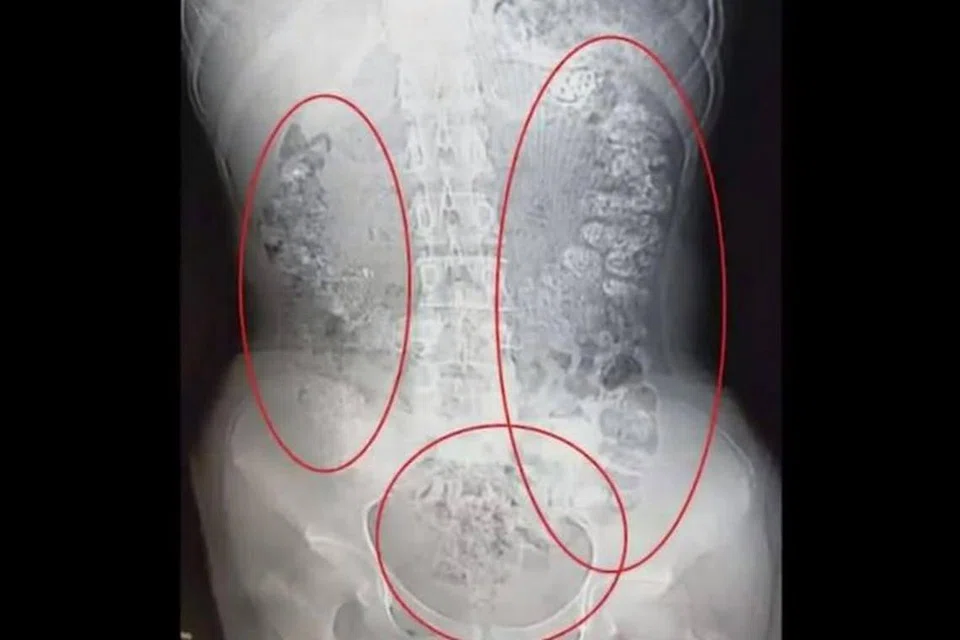

சீனாவில் 'பபுள் டீ' பானத்தை அருந்திவிட்டு ஐந்து நாட்களாக மலச்சிக்கலால் அவதி யுற்ற 14 வயது சிறுமி மருத்துவமனையில் சேர்க்கப்பட்டுச் சிகிச்சை பெற்றுவருகிறார். ஸிஜியாங் மாகாணத்தில் வசிக்கும் அவரால் ஒழுங்காக சாப்பிட முடியவில்லை. அதோடு வயிற்றுவலியால் அவர் அவதியுற்றார். கடந்த மாதம் 28ஆம் தேதி அச்சிறுமியின் பெற்றோர் அவரை மருத்துவமனையில் சேர்த்தனர்.அச்சிறுமியின் உடலில் ஏற்பட்ட செறிமானக் கோளாற்றுக்கான காரணத்தைக் கண்டறிய சிரமப்பட்ட மருத்துவர்கள், 'சிடி ஸ்கேன்' எனப்படும் மருத்துவப் பரிசோ தனையை மேற்கொண்டனர். அவரது வயிற்றுப் பகுதியில் வழக்கத்திற்கு மாறான உருண்டை வடிவிலான நிழல் இருப்பதுபோலப் பரிசோதனையில் தெரிய வந்தது.

அந்தச் சிறுமி அருந்திய 'பபுள் டீ' பானத்தில், மாவால் செய்யப்பட்ட நூற்றுக்கணக்கான உருண்டைகள் செறிமானமாகாமல் இருந்ததையே 'சிடி ஸ்கேனில்' பதிவான நிழல் காட்டியதாக மருத்துவர்கள் அறிந்தனர். தாம் என்ன சாப்பிட்டோம் என்பது பற்றி தொடக்கத்தில் வெளியில் சொல்ல தயங்கிய அச்சிறுமி, கடைசியில் உண்மையைக் கக்கினார்.